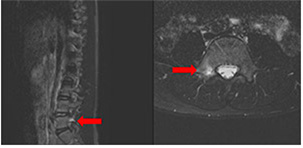

バレーボールや野球で多く見られる腰椎分離症もMRIであればすぐに診断できます。